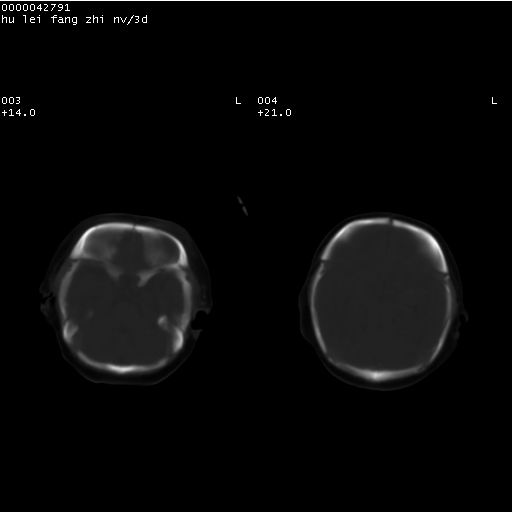

患儿 女,3天。惊跳,纳差。第二胎顺产,羊水ⅱ度。

临床诊断:hie?

颅脑ct轴位平扫(层厚、层距均为7mm),图像如下:

hie合并蛛网膜下腔出血

hie合并蛛网膜下腔出血,五、六脑室形成。

支持hie伴少量蛛血.

支持胼胝体发育不良。

支持hie,胼胝体发育差些